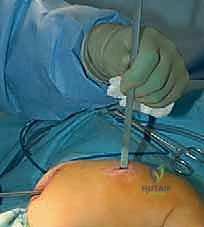

يتم إجراء العملية تحت التخدير العام. يتم وضع الطفل على طاولة العمليات الشفافة للأشعة، ويتم استخدام جهاز الأشعة السينية المستمر (C-arm) لضمان الدقة المطلقة خلال كل ثانية من العملية.

بدلاً من فتح الساق بالكامل، يقوم الدكتور هطيف بعمل ثقوب صغيرة جداً (مليمترات) في الجلد. باستخدام أدوات دقيقة جداً (مثل الإزميل الدقيق أو المثقاب المتخصص)، يتم قطع العظم في أماكن التقوس من الداخل دون إتلاف الأنسجة الرخوة أو العضلات المحيطة. هذا يحافظ على التروية الدموية للعظم (Periosteum)، مما يسرع من التئام العظم بشكل مذهل.

الخطوة الخامسة: الإغلاق والتجبير

نظراً لأن التدخل كان عبر ثقوب صغيرة، يتم إغلاقها بغرزة واحدة أو حتى بشريط لاصق طبي. يتم وضع جبيرة خفيفة أو دعامة لحماية الساق خلال الأسابيع الأولى من الالتئام. الألم يكون في حده الأدنى مقارنة بالطرق القديمة.